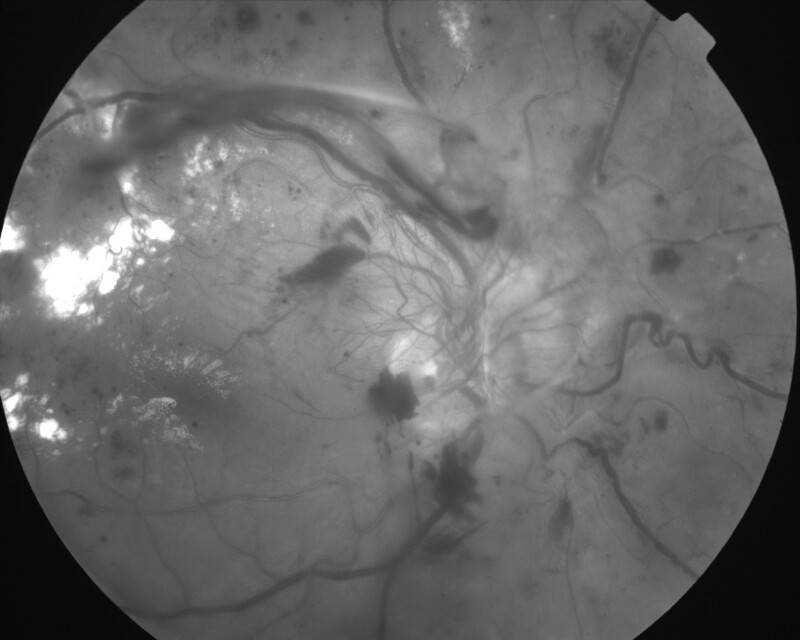

RETINOPATHIE DIABETIQUE PROLIFERANTE

IMG0004.JPG